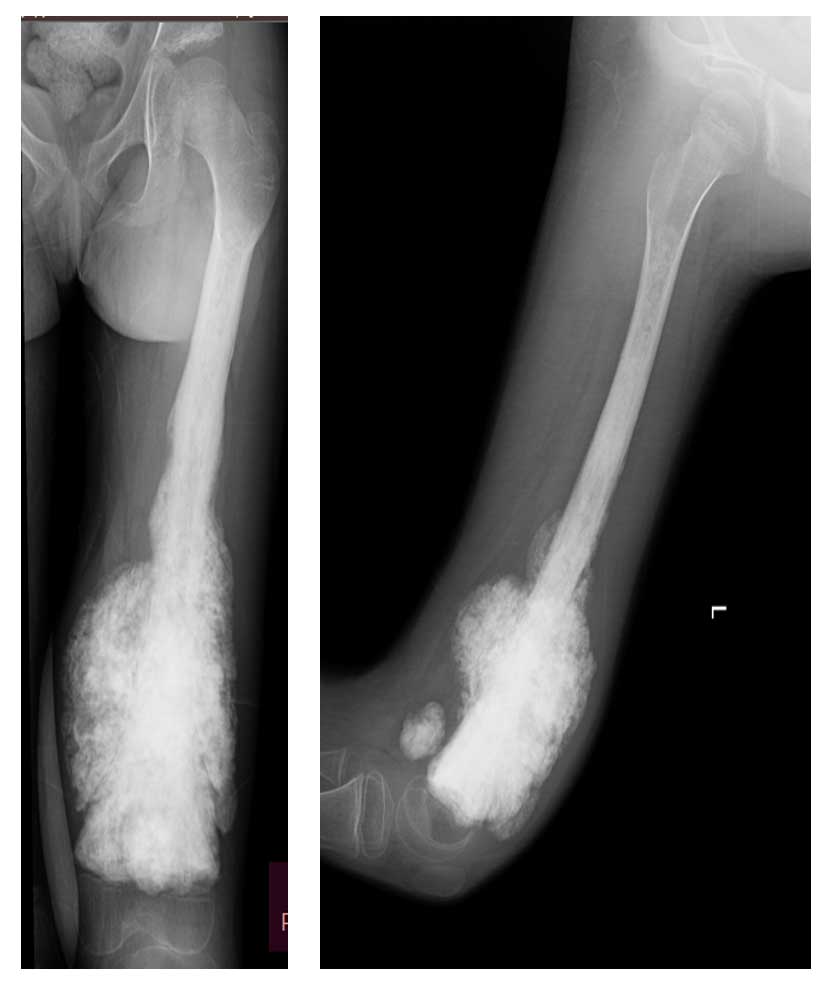

Ameliyat Öncesi: Röntgende femurun tamamına yakınını dolduran, distalde yumuşak dokuya uzanım gösteren düzensiz sınırlı sklerotik tümör dokusu görülmekte.